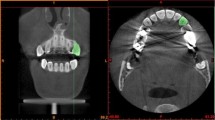

Physiologically accurate 3D models of a mandibular second molar and a maxillary central incisor were created in Solidworks (Dassault Systèmes) based on computer tomography (CT) data provided by eHuman, Inc. The CT data contained a point-cloud that traced surfaces of enamel, dentin and pulp chamber, as well as the interfaces between enamel and dentin. 3D CAD models were created by connecting the relevant points together and generating surfaces that passed through the said points and surfaces. The tooth models then include enamel and dentin components with a pulp chamber in the dentin. The present tooth geometries and periodontal ligament are shown in Fig. 1.

The solid models of these teeth were meshed for finite element analysis (FEA) in MSC Apex. The pre-processing, processing and post-processing steps were performed in MSC Marc/Mentat software. The finite element mesh that we developed for modeling a mandibular second molar is illustrated in Fig. 2. A percussion rod was also included in the present 3D models to simulate QPD accurately and for predicting the force measured by a sensor in the rod as a function of time. The present FEA meshes have a total number of about one million elements each. The location and angle of the percussion rod to each tooth was based on typical clinical use of the Periometer hand piece. For molars, the rod percussion is generally positioned at the buccal-mesial cusp since this is the easiest cusp on these teeth to access. This rationale was also used to apply similar percussion rod positioning for in vivo studies conducted previously [26,27,28,29].